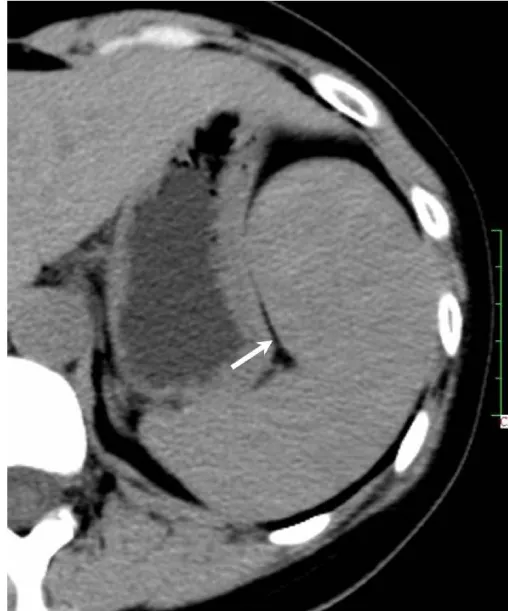

Solitary well-circumscribed masses were detected in all the five patients by ultrasound. One mass was of hypoecho, while the remaining masses were of hyperecho with posterior enhancement (Figure 1A). The maximum diameter ranged from 3.0 cm to 9.0 cm. At CT scanning, two masses appeared as hypodense (Figure 1B) and one was isodense (Figure 2A) to the normal spleenic parenchyma. In the two patients who received MR imaging, masses were isointensity at T1 weighted images (Figure 3A) and hypointensity with scattered sign void spots at T2 weighted images (Figure 3B). After intravenous injection of the contrast materials, all the five masses presented circle enhancement at arterial phase (Figure 3C and Figure 4A), while peripheral enhanced node was noted in one mass (Figure 2B). The circle enhancement persisted and radical line enhancement were observed at portal vein phase in 3 cases (Figure 1C) and progressive filling in was seen in two cases (Figure 2C). At delay phase of MR imaging, one lesion showed obvious enhancement with stellate low signal scar in the center comparing with surrounding splenic parenchyma (Figure 3D), while the other demonstrated central and circle enhancement to form a spoke-like appearance (Figure 4B). At delay enhanced CT scanning, two masses were isoattenuation to the surrounding splenic parenchyma (Figure 2D) and one lesion kept as hypoattenuation but with radial enhanced lines and enhanced circle to form a spoke-like appearance.

It usually affects middle-aged adults [6] and it is commonly found incidentally on radiographic imaging, or during operation for an unrelated condition. In present series, the patients are middle-aged adults without any related symptoms and the lesions were detected incidentally at routine ultrasound of health examinations. On ultrasound, manifestations of SANTs are vary widely from heterogeneous echo-texture with hyperechogenic, hypoechogenic, or isoechogenic appearing lesions, which are unspecific [7,8]. CT and MRI can show some characteristic features of SANTs, which include a solitary well demarcated mass with early peripheral enhancemant with radiating lines and progressive enhancement at the delay phase, and hypointens at T2 weighted MR images [2,3,5,9-13]. These features reflect the underlying pathological changes of scattered angiomatoid nodules separated and surrounded by sclerotic fibrotic stroma [10]. In present series, we also observed these characteristic features with well correlation to pathological findings. Circle and spoke-like enhancement can be contributed to fibrotic stroma surrounding and separating the angiomatoid nodules. The sclerotic fibrotic stroma may also result in isodense on CT, isointensity on T1 weighted images and hypointensity on T2 weighted images of MR imaging. The signal void spots at T2 weighted MR images have not been described at other literatures and may be contributed to hemosiderin deposition due to magnetic susceptibilty artifact.